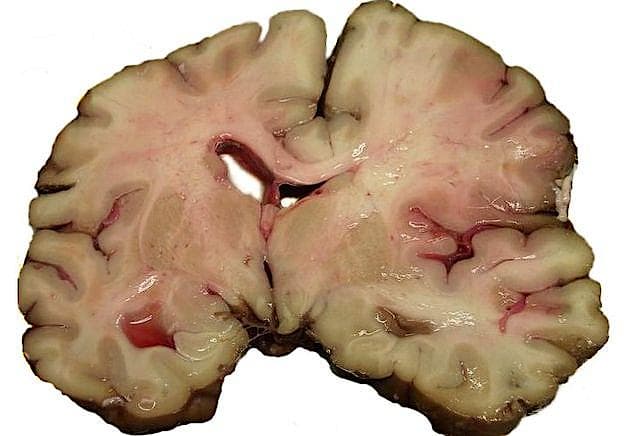

Danskere med små indtægter har betydeligt større risiko for at blive ramt af en blodprop i hjernen (iskæmisk stroke) end borgere med høje indkomster.

I undersøgelsen analyseres 54.048 patienter, som fra 2003-2012 blev indlagt på danske hospitaler til behandling for iskæmisk stroke.